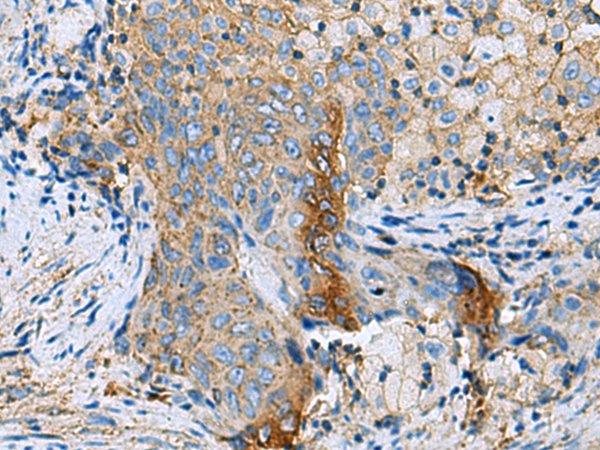

分类: 科研抗体货号: P10293别名: PLC-beta-2应用: IHC反应种属: Human, Mouse, Rat